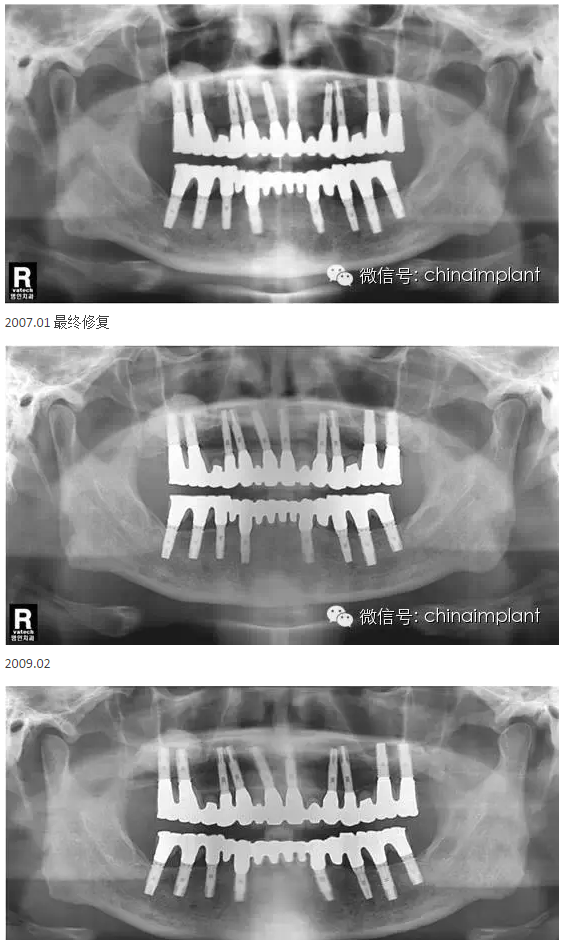

之前針對(duì)全口無(wú)牙進(jìn)行種植修復(fù)的案例中,因?yàn)轭M骨的原因,后期使用橋冠修復(fù)時(shí),一般是3部分(兩側(cè),磨牙,前牙),最近的案例中修復(fù)是一般都是做一體式的橋冠,現(xiàn)在從臨床的修復(fù)案例來(lái)看,沒有什么問(wèn)題。

本案例已經(jīng)將近10年了(2005年12月),但是修復(fù)效果個(gè)人認(rèn)為很不錯(cuò),所以拿出來(lái)和大家分享。

從修復(fù)全景片上看到牙齒排列非常好